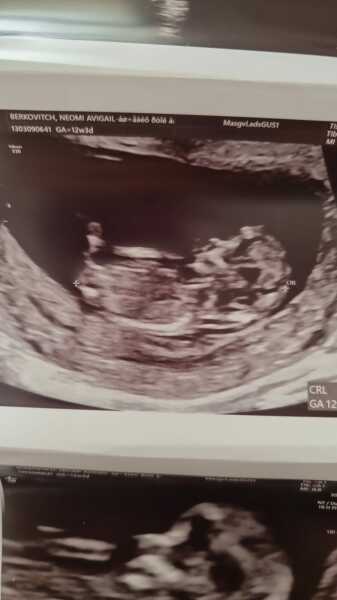

Naomi456 · 21/07/2024 10:59

Hi everyone!

I had ultrasound at week 12+1

And they told me its a boy.

Wish for a girl!!

Do I have any chance??

I have a pic from the ultrasound.

Still praying...